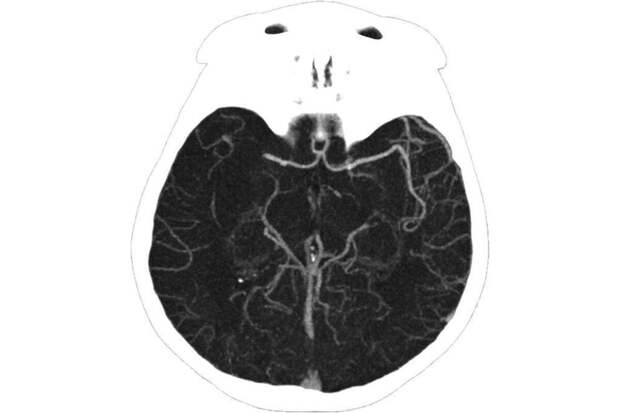

25-летняя женщина поступила в ГКБ им. М.П. Кончаловского с жалобами на головокружение, слабость и онемение конечностей. Медики диагностировали у нее ишемический инсульт.

"Из артерии удалось извлечь червеобразный сгусток длиной 25 см. Изначально мы даже заподозрили, что в сосуде мозга женщины поселился паразит. Но исследования показали, что это все-таки тромб", — рассказал руководитель регионального сосудистого центра Владимир Кузнецов.

После операции пациентка прошла углубленное обследование, которое показало, что у нее развилось опасное аутоиммунное заболевание — антифосфолипидный синдром, при котором возрастает риск образования тромбов в артериях и венах. Женщине подобрали лечение, которое в дальнейшем будет препятствовать образованию тромбов.